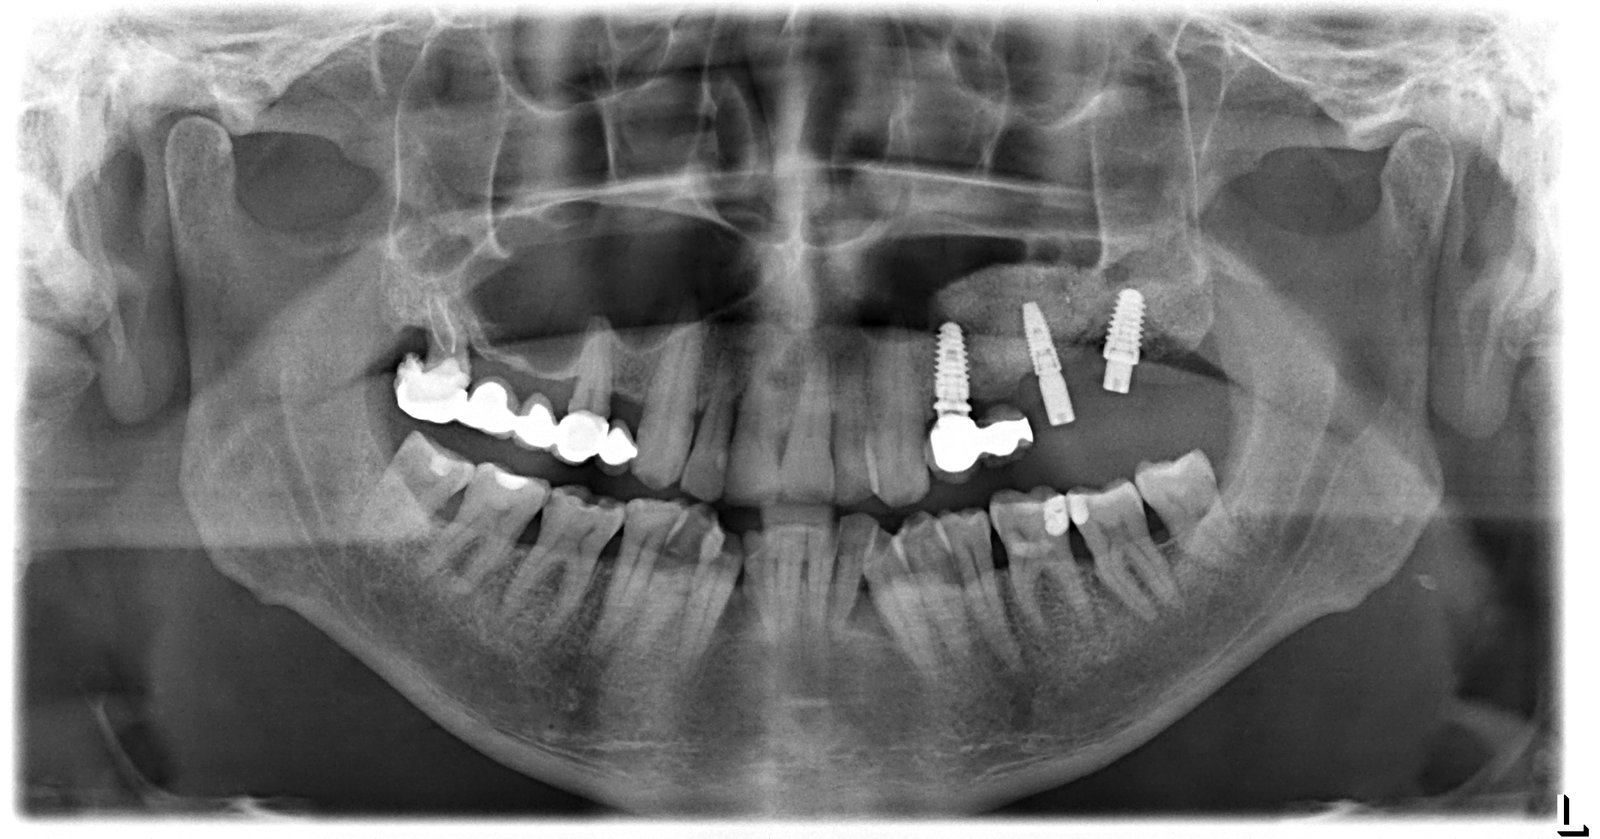

Paciente que acude a nuestra consulta con 8 implantes puestos en Brasil. En el traslado ha perdido la cartilla de id de los implantes y la clinica ha cerrado. Pudo [...]